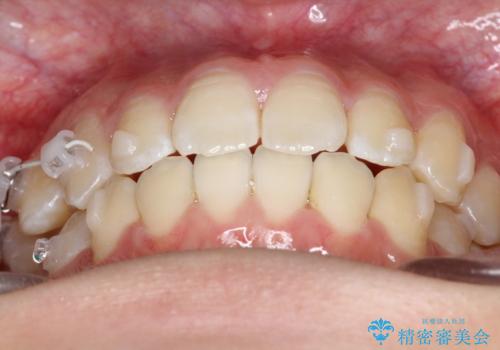

右上小臼歯の捻転を改善|インビザラインと部分ワイヤー矯正のコンビネーション治療

- 右上の小臼歯が大きくねじれており、噛み合わせや見た目に影響を与えている状態でした。診察の結果、インビザライン単独では十分な回転が得られにくいと判断。そのため、基本的な歯列の移動はインビザラインで行いながら、部分的にワイヤー矯正を併用するコンビネーション治療を計画しました。

まず、インビザラインで歯列全体を整えながら、スペースを確保しました。その後、部分ワイヤーを装着し、右上小臼歯の捻転を効率よく改善。ワイヤーの力を活用することで、より確実に歯の向きを整えることができました。治療後は、「しっかり噛めるようになり、見た目も自然になった」と患者様にもご満足いただきました。